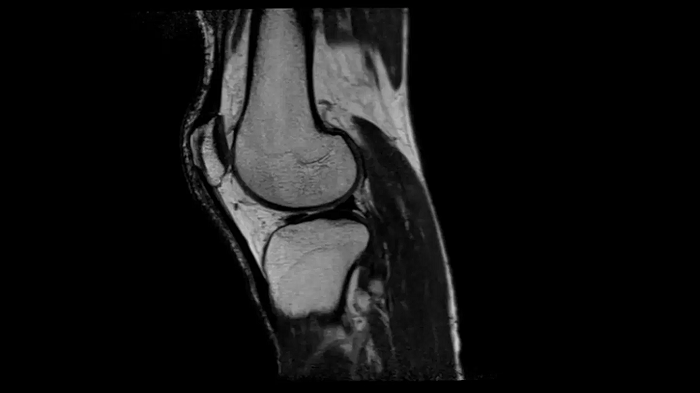

PD TSE Fat Sat with Deep Resolve and Simultaneous Multi-Slice

For clear imaging of the knee, brilliant fat suppression and performance are possible. Integrating the influence of Deep Resolve with the proven Simultaneous Multi-Slice technique.

SMS 2 | Deep Resolve Gain & Sharp

0.3 x 0.3 x 3.0 mm2

TA 2:16 minutes

MAC-ID: 7aaaa0198.